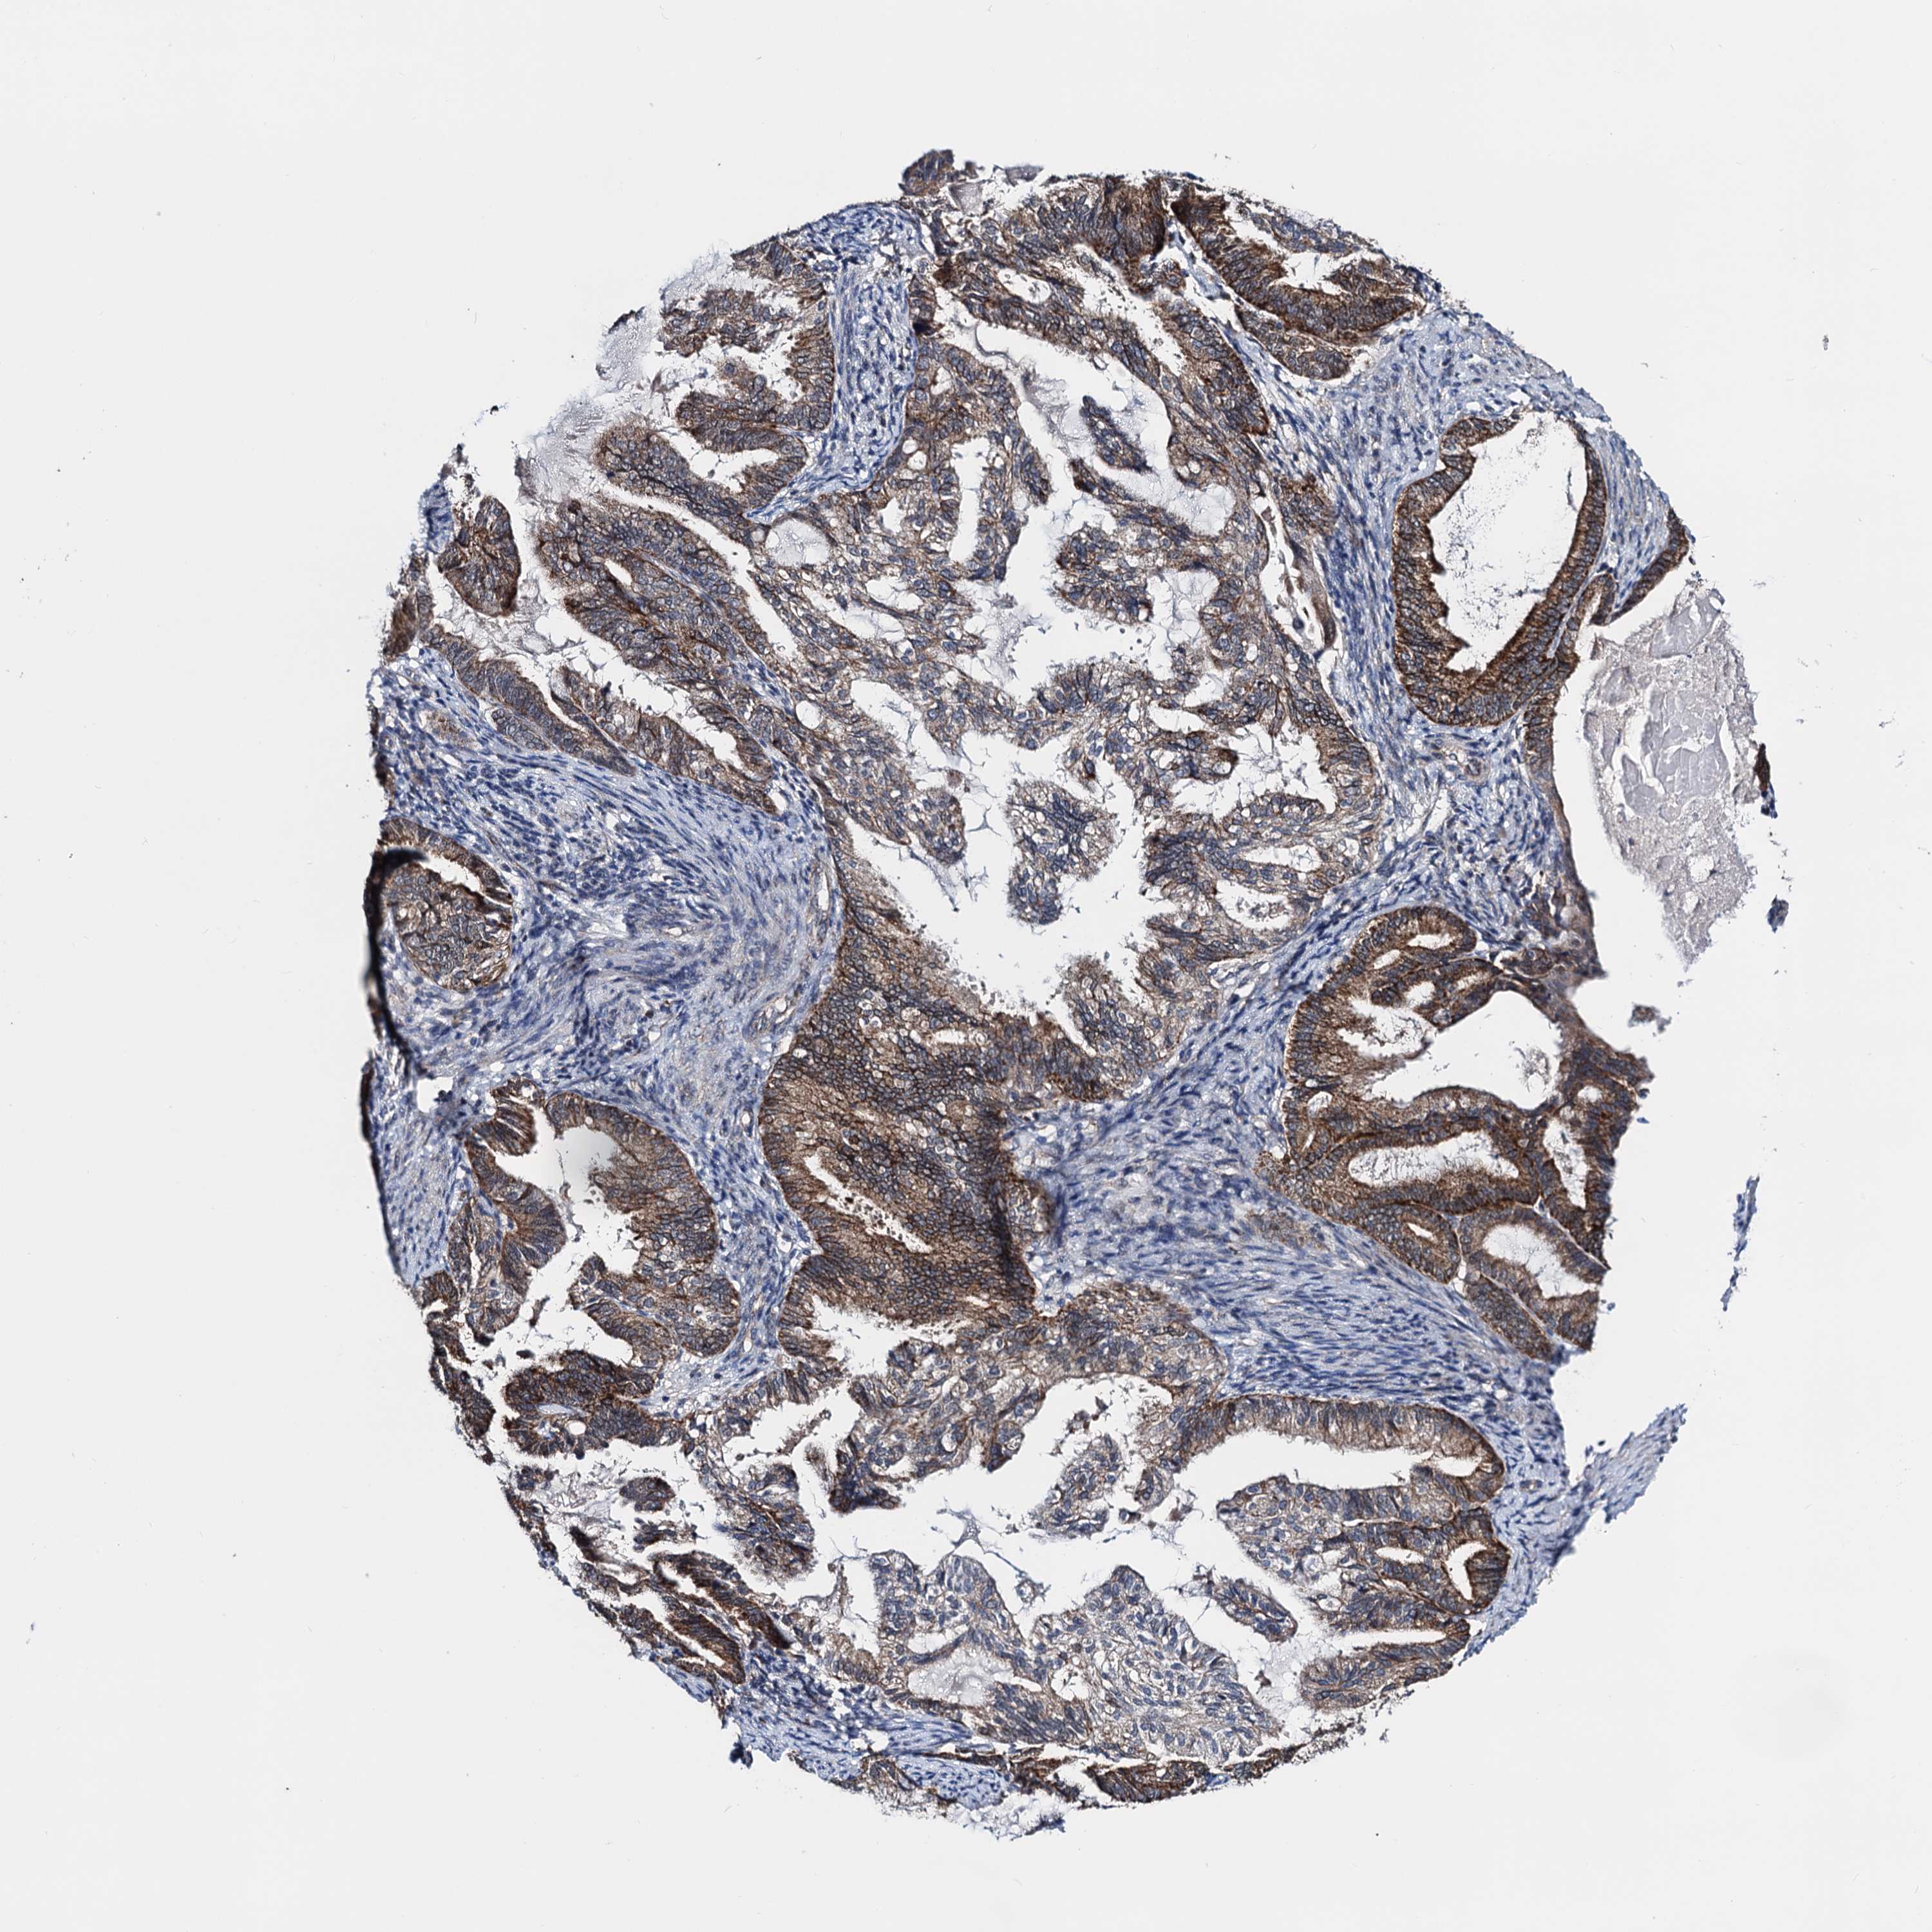

ENDOMETRIAL CANCER - Protein expressioni

A mouse-over function shows sample information and annotation data. Click on an image to view it in a full screen mode. Samples can be filtered based on level of antibody staining by selecting one or several of the following categories: high, medium, low and not detected. The assay and annotation is described here.

Note that samples used for immunohistochemistry by the Human Protein Atlas do not correspond to samples in the TCGA dataset.

Antibody stainingi

Antibody staining in the annotated cell types in the current human tissue is reported as not detected, low, medium, or high, based on conventional immunohistochemistry profiling in selected tissues. This score is based on the combination of the staining intensity and fraction of stained cells.

Each image is clickable and will lead to virtual microscopy that enables deeper exploration of all samples and also displays staining intensity scores, fraction scores and subcellular localization as well as patient and tissue information for each sample.

Antibody HPA040126

Staining

High

Medium

Low

Not detected

Intensity

Strong

Moderate

Weak

Negative

Quantity

>75%

75%-25%

<25%

None

Location

Nuclear

Cytoplasmic/membranous

Cytoplasmic/membranous,nuclear

Adenocarcinoma, NOS